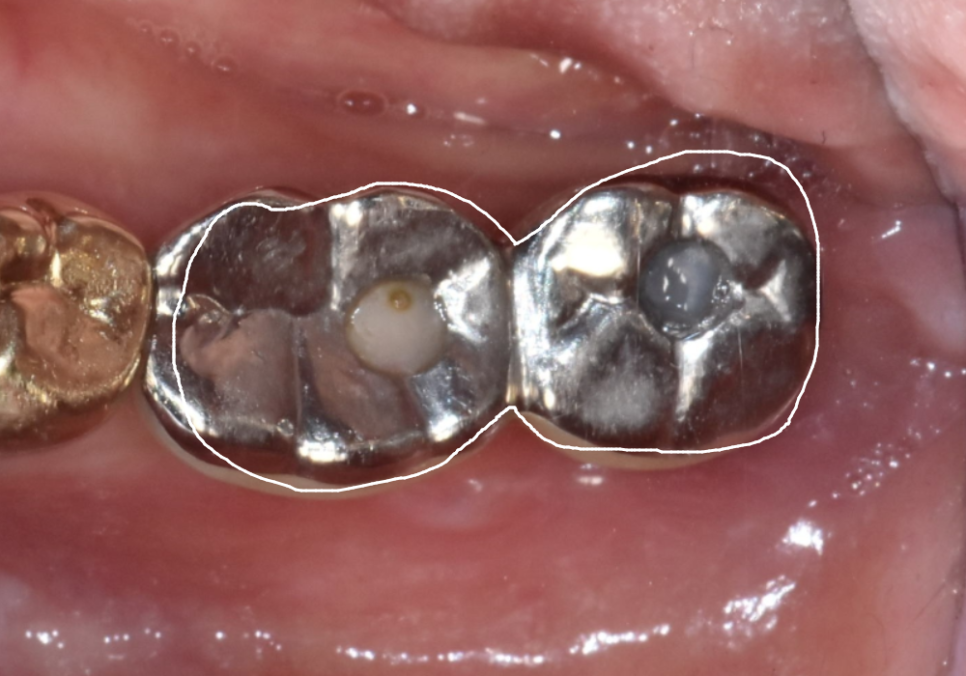

왼쪽 아래에 오래전에 심은

임플란트 2대가 있었는데,

맨 끝 쪽 임플란트(#37) 주변 잇몸에서

고름이 새어 나오고 있었고

잇몸 밖으로 임플란트 뿌리가

드러나 있었습니다.